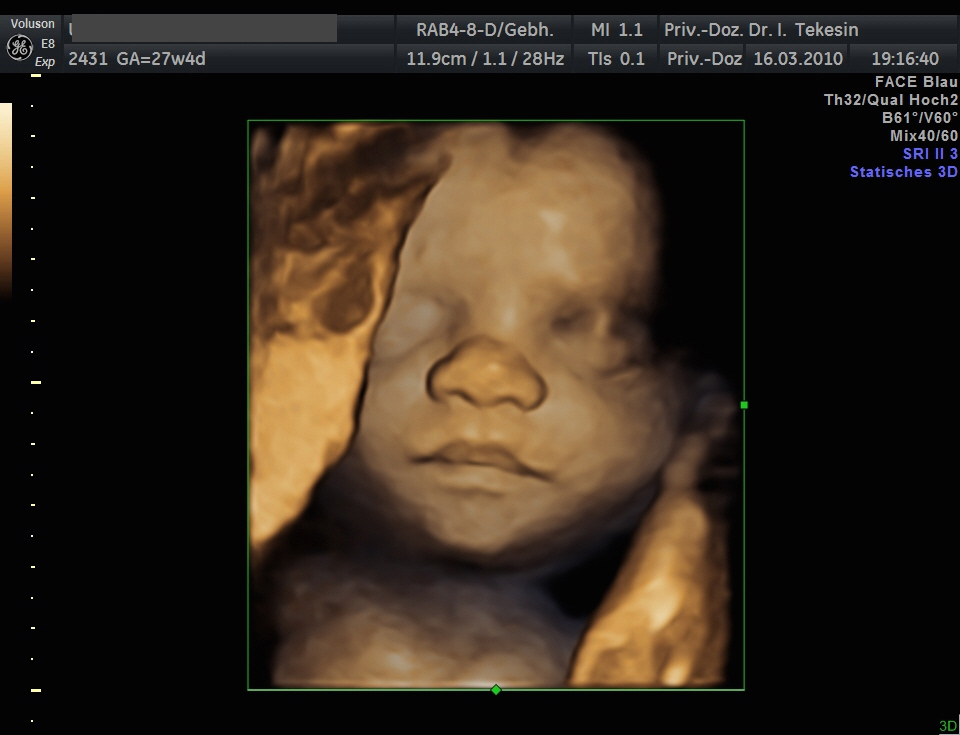

3D-/4D-Ultraschall (optional)

Immer mehr werdende Eltern interessieren sich für die faszinierenden Bilder, die dieses Verfahren liefert. Die plastische, dreidimensionale Darstellung der Oberfläche des Gesichts und anderer Körperregionen wird durch spezielle Bildrekonstruktion in schnellen Rechnern erreicht. Auch einzelne innere Organe oder „Gefäßbäume“ können von allen Seiten betrachtet werden. Viele dünne Schnittebenen (2D) werden zu einer gemeinsamen 3D-Sichtweise im Computer des Ultraschallgerätes zusammengeführt. Unter einem 4D-Ultraschall versteht man darüber hinaus eine 3D-Ultraschalluntersuchung unter Echtzeitbedingungen. Anstatt nur statische Bilder anzuzeigen, erfasst ein 4D-Ultraschall die Bewegungen des Kindes, weshalb er auch als „Live-3D-Ultraschall“ bezeichnet wird.

Diese Vorgehensweise ermöglicht äußerst realistische Bilder, bei denen sogar Gestik und Mimik des Kindes in bewegten Sequenzen festgehalten werden können. Die Untersuchung kann wie auch der normale Ultraschall während des gesamten Schwangerschaftszeitraums durchgeführt werden. Möchte man das Ungeborene komplett sehen, wird die 12. bis 16. Schwangerschaftswoche empfohlen, die Zeit zwischen der 28. und 33. Schwangerschaftswoche eignet sich besonders zur präzisen Darstellung einzelner Körperteile

Wir sehen in diesem modernen Verfahren in erster Linie eine ergänzende Maßnahme bei speziellen Fragestellungen bezüglich Herz, Gehirn oder Skelett und vor allem bei Verdacht auf eine fetale Besonderheit.

Kind in der 28. Woche (3D-Darstellung)